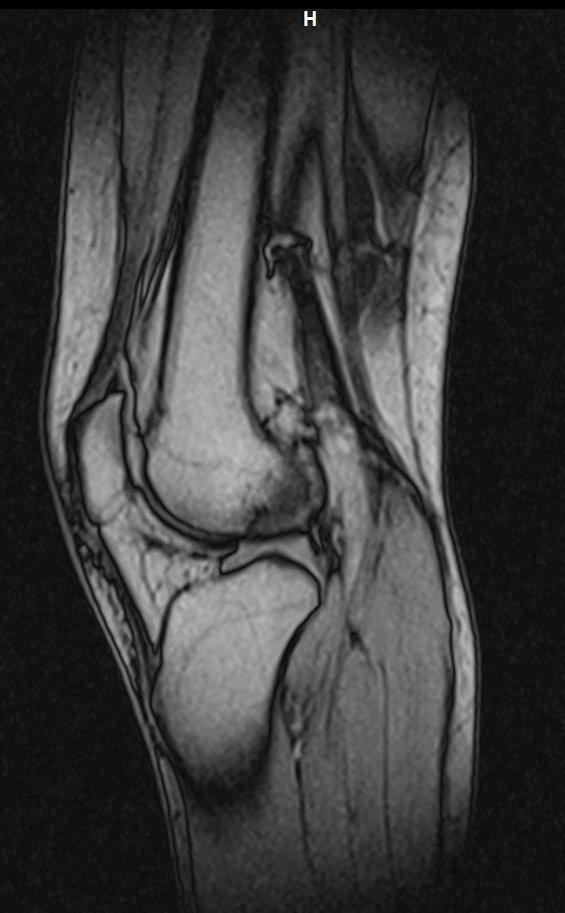

Здравейте, тъй като незнам как да ви кача целия диск Ви качвам малко снимки

Здравейте, благодаря за ЯМР-а.

Подборът на срезове/снимки не е най- добрият. Моля да изпратите диска на имейл: infо@beta-clinic.com или чрез спедитор на адреса на Бета клиник.